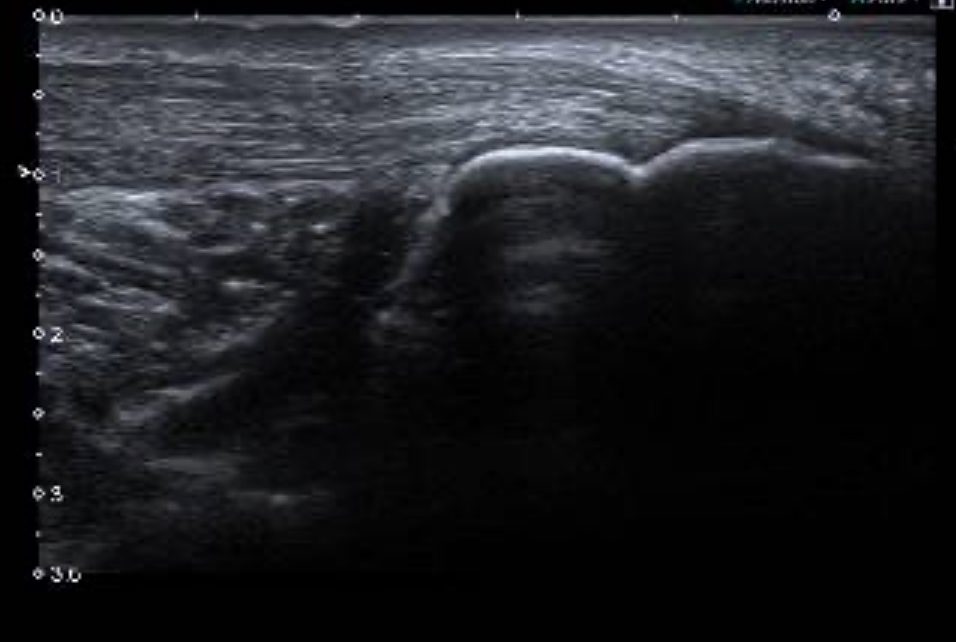

En la segunda imagen vemos en corte transversal una imagen con contenido hipoecogénico que corresponde con la zona de rotura tendinosa. Por último en la tercera imagen vemos la inserción tendinosa en el calcáneo conservada.